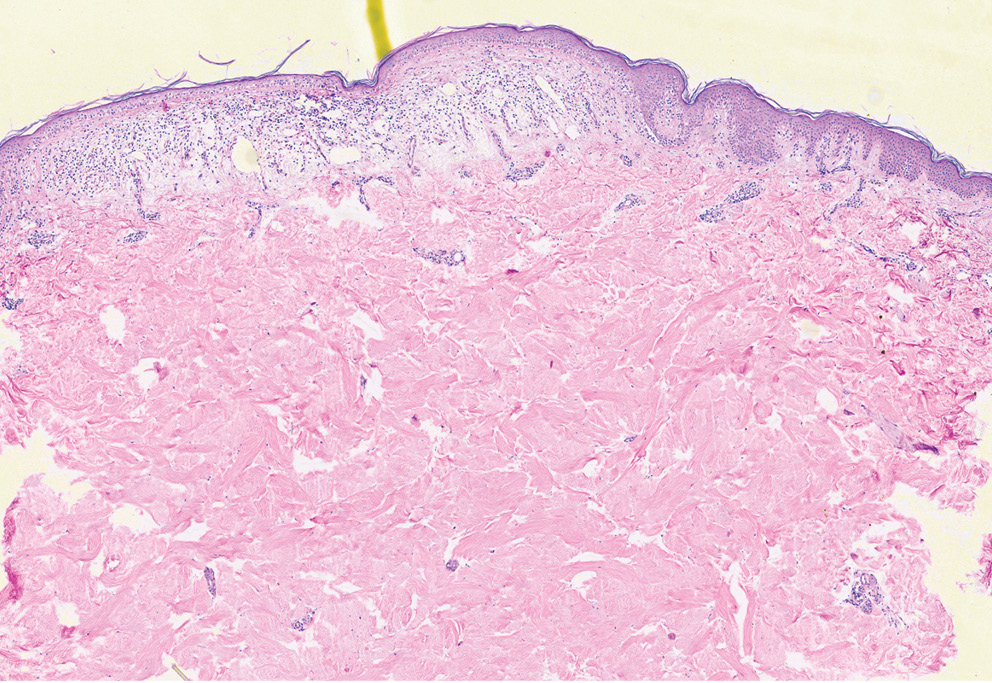

В октябре 2021 г. выполнена биопсия кожи. По результатам гистологического исследования от 02.11.2021 заключение: гиперкератоз, эпидермис со склонностью к атрофии, отек верхней части дермы, сосуды расширены, в верхней части дермы диффузно-очаговый лимфоцитарно-гистиоцитарный инфильтрат, отдельные клетки инфильтрата проникают в эпидермис (рис. 3).

Рис. 3. Гистологическое исследование от 02.11.2021 (окраска гематоксилином и эозином; ×40). Гиперкератоз, эпидермис со склонностью к атрофии, отек верхней части дермы, сосуды расширены, в верхней части дермы диффузно-очаговый лимфоцитарно-гистиоцитарный инфильтрат, отдельные клетки инфильтрата проникают в эпидермис

Fig. 3. Histological examination dated 02.11.2021 (stained with hematoxylin and eosin; ×40). Hyperkeratosis, epidermis with a tendency to atrophy, edema of the upper dermis, dilated vessels, diffuse focal lymphocytic-histiocytic infiltrate in the upper dermis, individual cells of the infiltrate penetrate the epidermis